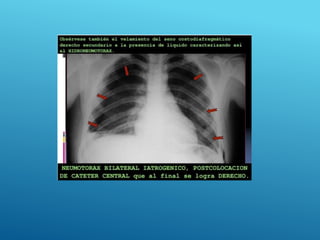

HEMOTÓRAX DERECHO

HEMONEUMOtórax

24/03/2017